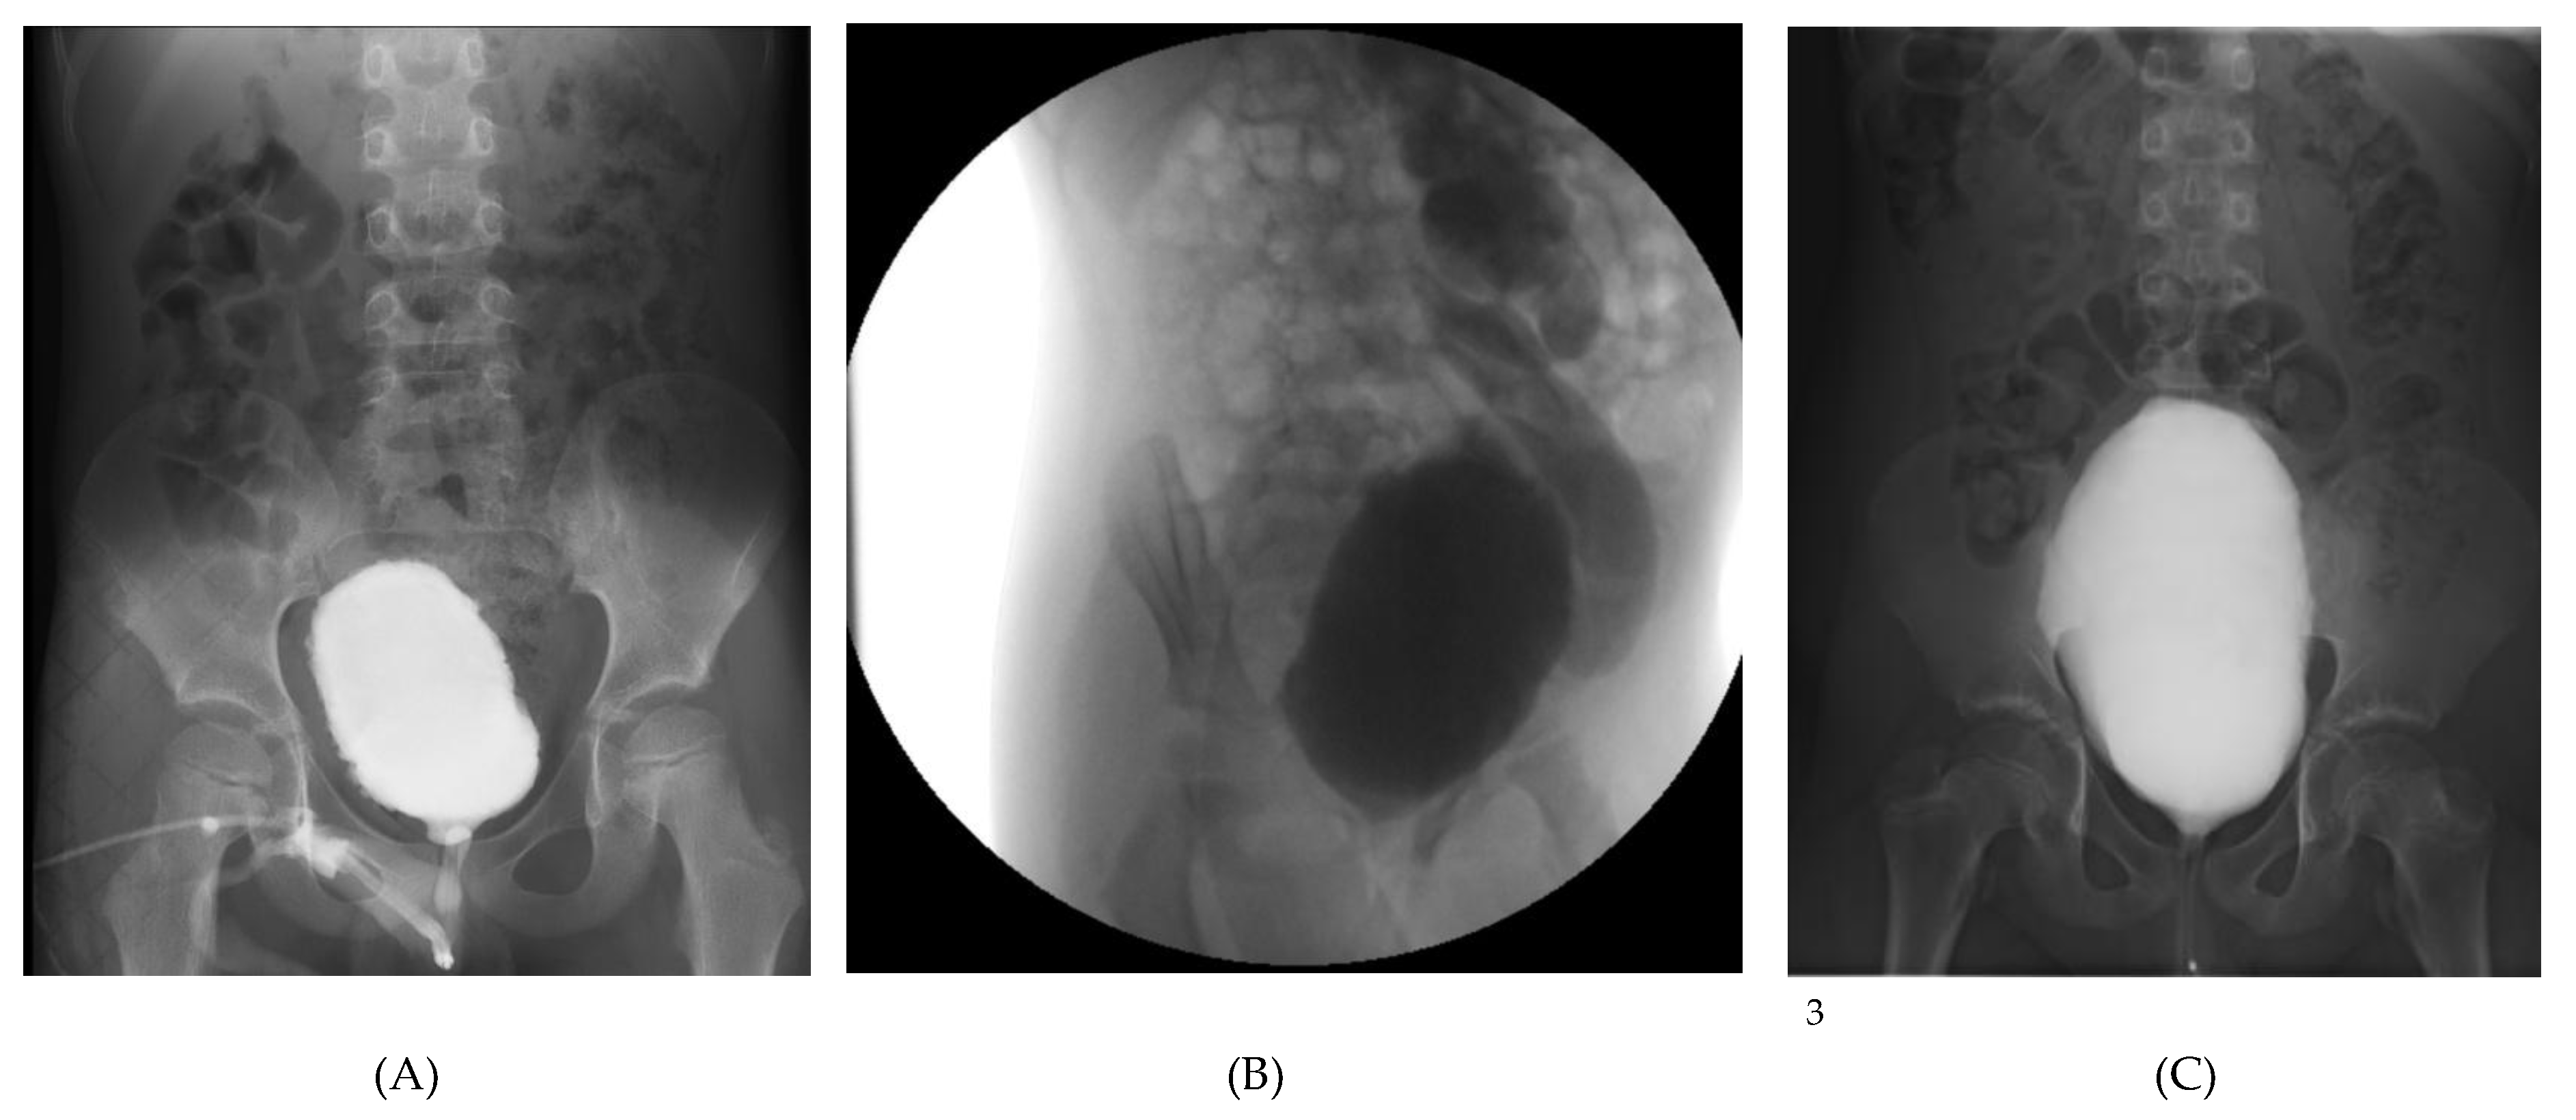

| VCUG Findings | Crenulated bladder, no reflux, normal emptying | Grade V left VUR, dilated tortuous ureter, no voiding achieved | Large-capacity bladder, mild crenulation, grade I VUR, incomplete emptying |

| Cystoscopy Findings | Deep trabeculations, pseudopolypoid mucosa, diverticula, dilated vessels | Marked trabeculation, cell-like and columnar mucosa, difficult ureteric visualization | Trabeculated, pseudodiverticular bladder mucosa, normal urethra |

| Urodynamic Pattern | Detrusor overactivity, reduced capacity, uninhibited contractions | Poor compliance, detrusor–sphincter dyssynergia, high PVR | Hypocontractile detrusor, weak flow (Qmax 4 mL/s), high PVR |

| Diagnosis | Severe functional LUTD | Hinman syndrome (non-neurogenic neurogenic bladder) | Functional LUTD with hypocontractile bladder |